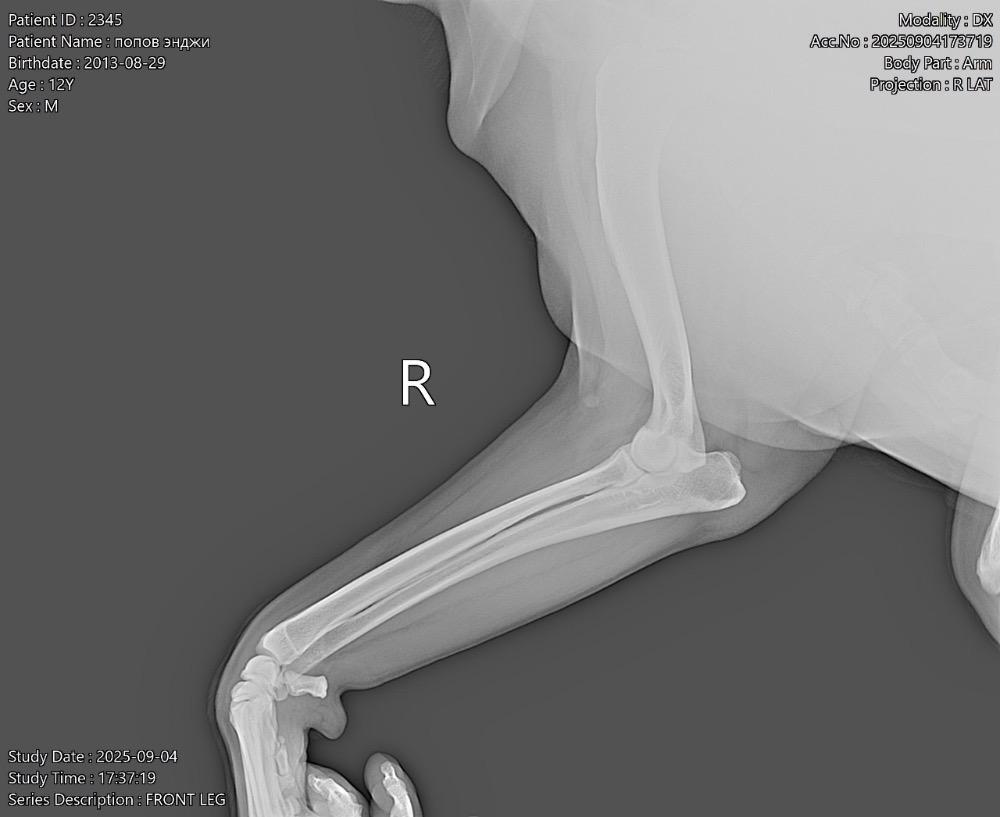

Татьяна13 Опубликовано 24 ноября, 2025 Опубликовано 24 ноября, 2025 (изменено) Всем здравствуйте! В июне началась проблема с лапами. Поставили диагноз-остеоартрит! Робексера+пк мерц прекрасно справлялись! На прошлой неделе собаке резко стало худо. Она начала часами без остановки дышать, иногда пристанывая. Было ясно, собаку что-то беспокоит…. В ветеринарке сдали анализ крови, сделали узи брюшной полости-ничего критичного… Врач решил, что Робексера уже не помогает, заменили на Фироко 227 мг + также оставили пк мерц. Добавили усросан, чтоб чуть полечить печень, так как небольшие отклонения есть… За 3 дня улучшений не вижу. Собака все также дышит без остановки часами, иногда пристанывая, второй день отказывается от корма (но вкусняшки ест), воду из миски пить отказывается (но пьет в ванной из душа и ест снег). Сегодня как будто начали отказывать задние лапы-она волочит ими. Вновь погнали в ветеринарку, они настаивают, что Фироко препарат хороший, сильнее его уже нет. Ждите! Чего ждать? Обезболивающее должно действовать же сразу…. Сказали, что тут скорее всего произошло защемление позвонка! Поэтому задние лапы не слушаются! И либо опять же ждите, либо делайте мрт, а потом операцию (собаке без пяти минут 12 лет, кстати!). Вдобавок выписали: Габапентин. В четверг хотят еще прокапать Хиовет. Сейчас, солнце мое спит, ходить не может. Когда просыпается, пытается встать и начинает дико плакать! И снова ложится! Люди, чем помочь собаке моей? Столько таблеток выписали… Как не навредить😭 У меня уже сердце болит… Изменено 24 ноября, 2025 пользователем Татьяна13 1